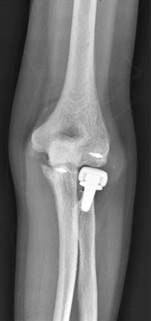

Figura 1: Prótesis de cabeza radial sobredimensionada, apreciándose un mayor espacio articular ulnohumeral lateral y falta de continuidad de la superficie protésica con el borde articular coronoideo.

Doce pacientes (25.53%) mostraron signos radiológicos de sobredimensionamiento protésico a lo largo del seguimiento, encontrándose la superficie de la cabeza radial proximal al borde lateral de la apófisis coronoides en la proyección anteroposterior. De estos casos, sólo cinco pacientes manifestaron sintomatología asociada. En un caso se apreció infradimensión protésica, sin significación clínica. Respecto a otras alteraciones radiológicas, 19 pacientes (40.4%) mostraron durante su seguimiento signos de radiolucencia periprotésica, principalmente alrededor del vástago, en su zona más proximal. No obstante, solamente seis de estos pacientes presentaron progresión de estas alteraciones hasta llegar a provocar aflojamiento sintomático (en cuatro pacientes) o dolor continuo.

Respecto a los tres casos con sobredimensión protésica, han sido incluidos dentro de complicaciones postoperatorias debido a su asociación clínica con dolor significativo y rigidez articular a pesar de la rehabilitación postoperatoria, pues se apreciaron sobredimensionamientos radiográficos hasta en 12 pacientes. En el presente estudio, hemos utilizado como referencia postoperatoria para detectar sobredimensionamientos la continuidad de la superficie protésica proximal con la articulación ulnohumeral en las radiografías anteroposteriores postoperatorias. Si se apreciaba un gap en la articulación ulnohumeral lateral respecto a la medial river delta sign, se consideraba que la prótesis estaba sobredimensionada. Diversos estudios ponen en duda la fiabilidad de este método de medición,31 como el de Rowland et al.,35 en el que ponen de manifiesto que el espacio articular ulnohumeral lateral es más amplio que el medial en un porcentaje considerable de la población. Esto puede habernos llevado a sobreestimar en cierta medida el número de casos con prótesis sobredimensionadas de nuestro estudio, sobre todo teniendo en cuenta la ausencia de sintomatología de muchos pacientes. No obstante, se ha utilizado esta referencia ante la ausencia de alternativas contrastadas de medición en el momento actual.